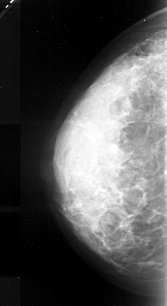

A_1052_1.LEFT_MLO

A_1052_1.LEFT_CC

LEFT_CC LINES 4276 PIXELS_PER_LINE 2326 BITS_PER_PIXEL 16 RESOLUTION 42 NON_OVERLAY

LEFT_MLO LINES 5116 PIXELS_PER_LINE 2686 BITS_PER_PIXEL 16 RESOLUTION 42 NON_OVERLAY